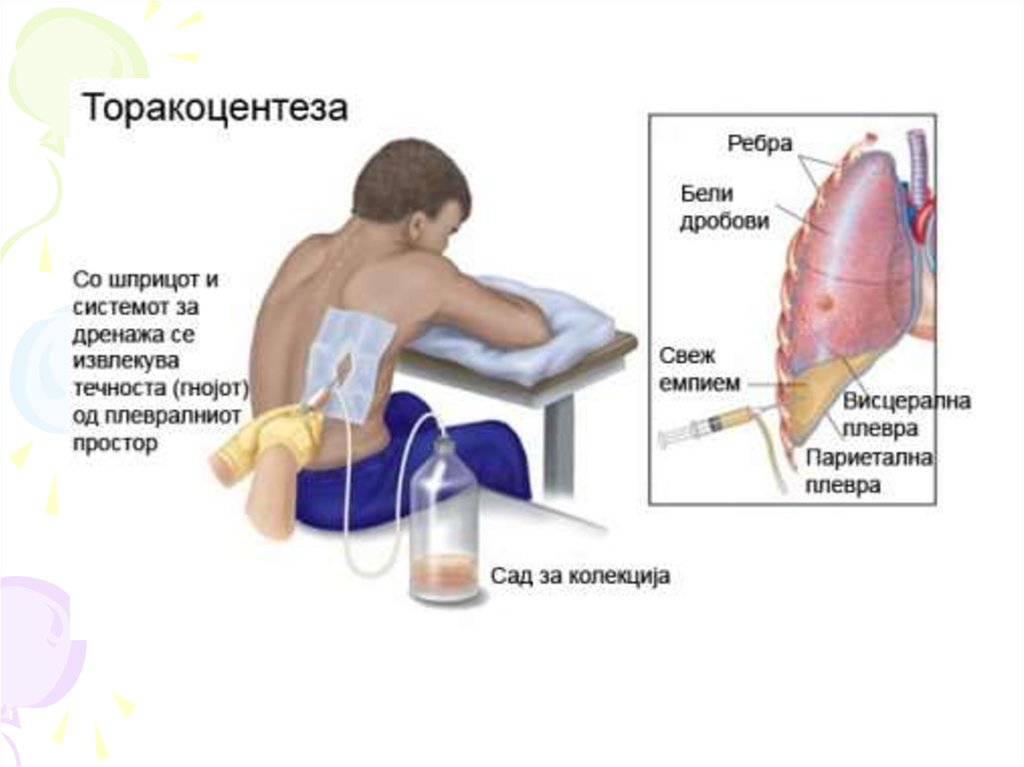

Симптомы и причины скопления воды в легких